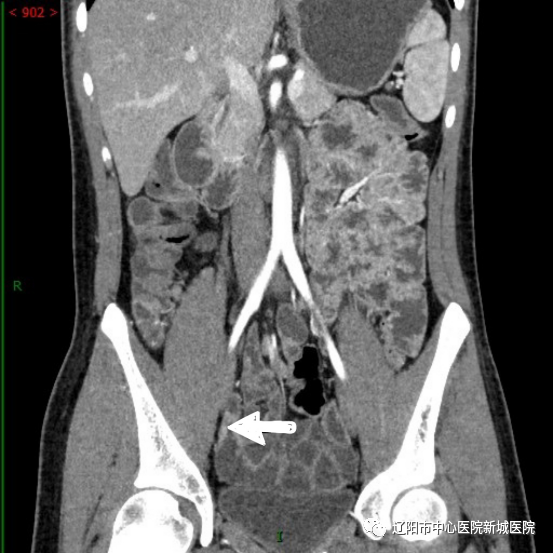

小腸腸壁節(jié)段性增厚并明顯均勻強(qiáng)化,管腔狹窄

腸系膜淋巴結(jié)腫大